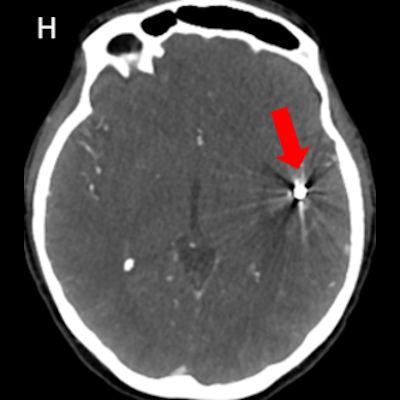

- Kontrastsız BT görüntülemede (E) bu düzeyde intraparankimal kanama ile uyumlu hiperdens alan gözleniyor (ok).

- DSA görüntülemede (G) sol MCA M2 segmentinde anevrizmatik dolum fazlalığı izleniyor (ok). Bu anevrizmaya eş zamanlı koil işlemi yapılıyor (oklar) ve işlem sonrası kontrol BT anjiografi görüntüsünde (H) metalik koil materyali izleniyor (ok).